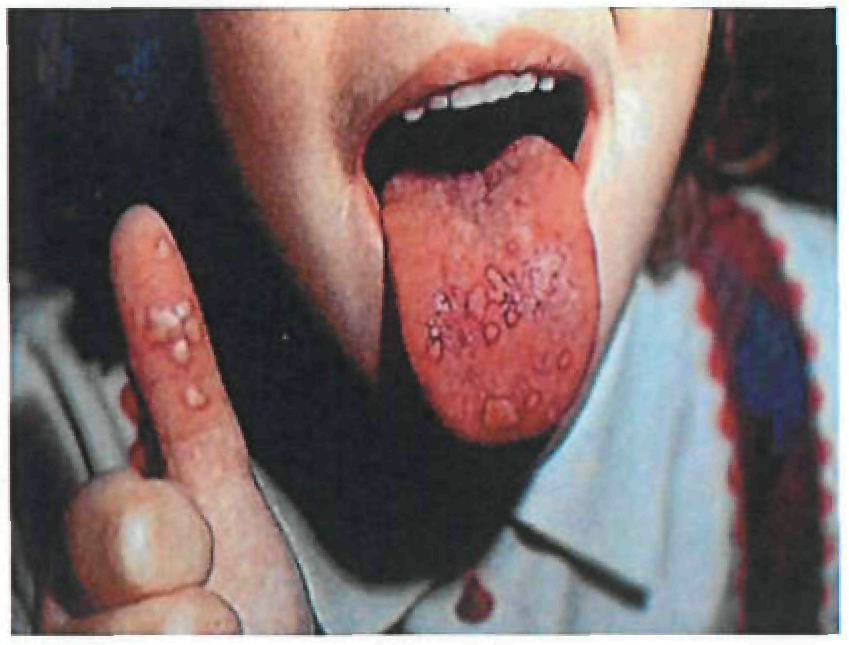

Период высыпаний

На 3-4-й день болезни температура тела снижается до субфебрильной, одновременно на коже головы (прежде всего на лице) и на слизистых оболочках полости рта, гениталий, конъюнктивы, роговицы глаз появляются необильные элементы сыпи. Энантема на слизистых оболочках полости рта обычно предшествует появлению экзантемы. Первые элементы сыпи обычно появляются на лице, быстро распространяясь на верхние конечности, а затем - на туловище и нижние конечности, поражая ладони и подошвы. Распространение экзантемы имеет центробежный характер - на туловище элементов меньше, чем на лице и конечностях.

Высыпания эволюционируют через стадии:

- макула (пятно) (1-2 дня);

- папула (узелок) (1-2 дня);

- везикула (пузырек, заполненный прозрачной жидкостью) (1-2 дня);

- пустула (гнойничок) с пупковидным вдавлением в центре (5-7 дней);

- корочка (7-14 дней).

В 70-80% случаев сыпь характеризуется мономорфностью, в остальных случаях может отмечаться полиморфизм [38]. На одном участке кожи сыпь всегда мономорфна.

В 95% случаев сыпь поражает лицо, в 75% - ладони и подошвы, что является отличительным признаком заболевания. Также поражаются слизистые оболочки полости рта (в 70% случаев), половые органы (30%), конъюнктива и/или роговица (20%). У части пациентов имеет место проктит с поражениями перианальной области изолированно или в сочетании с высыпаниями в области гениталий [39]. Количество элементов сыпи варьирует от единичных до нескольких тысяч [13].

| Энтеровирусный везикулярный стоматит с экзантемой | За 12-24 часа до сыпи | К концу 1-го дня болезни | Пятна или папулы, которые быстро превращаются в везикулы. При вскрытии везикул образуются эрозии, которые покрываются корками и регрессируют. На слизистой полости рта пятна превращаются в сероватые везикулы, которые вскрываются с образованием мелких болезненных язв с отвесными краями. Болезненные папулы на ладонях и подошвах. | Пятна, папулы - диаметр 0,2-0,8 см, язвы 0,5-1,0 см | Этапность распространения не характерна | Как правило, отсутствует | Твёрдое нёбо, язык, слизистая оболочка щёк. Ладони, подошвы, боковые поверхности пальцев рук и ног, ягодицы. |